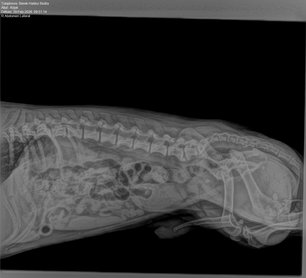

Az időpontra megérkezve Kópét azonnal megvizsgálták, ultrahangos és röntgenvizsgálatot végeztek, melyeket vér- és vizeletvétel követett. Sajnálatos módon a vizsgálatokat követően kiderült, hogy Kópé állapota nagyon súlyos. Az orvos nagyon lelkiismeretesen és részletesen felvázolta nekünk a helyzetet: a kutyám hólyagjában 10–12 darab, 0,3–1,3 cm-es kő található, melyeket el kell távolítani. A medencetájékon és a húgyvezetéken áthaladó kő kipisilése lehetetlennek tűnt, így az egyetlen megoldás a kasztrálás és a húgyvezeték hátra- illetve kivezetése egy sztómán keresztül. A műtétet követően Kópé úgy fog pisilni, mint a lány kutyák.